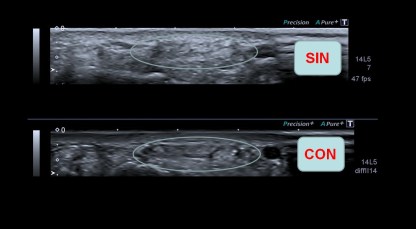

Tocamos la espina escapular, cerca del húmero en el teórico lugar de la inserción del Infraespinoso y colocamos la sonda como os marco en la imagen, siempre debajo de la espina escapular, entonces tienes que buscar estas dos imágenes que te pongo a continuación juntas:

Imágenes del protocolo

En la imagen ves dos imágenes, la de arriba es justo en la inserción, la de abajo es la imagen que tienes que conseguir para ver y estudiar el Labrum posterior, para eso deberás hacer un recorrido mínimo hacia la columna vertebral siguiendo el eje largo del músculo infraespinoso, sí, es dificil, me encantaría guiarte con la mano, pero de momento nos apañamos así.